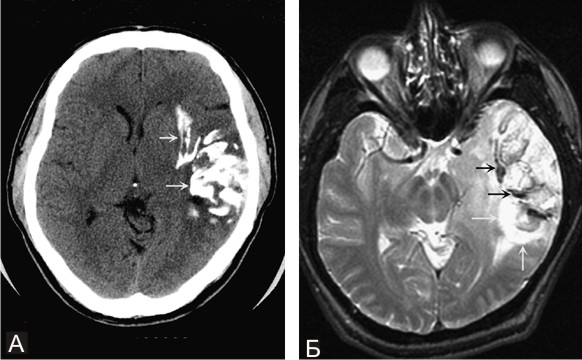

D33 Доброкачественное новообразование головного мозга и других отделов центральной нервной системы

Олигодендроглиома